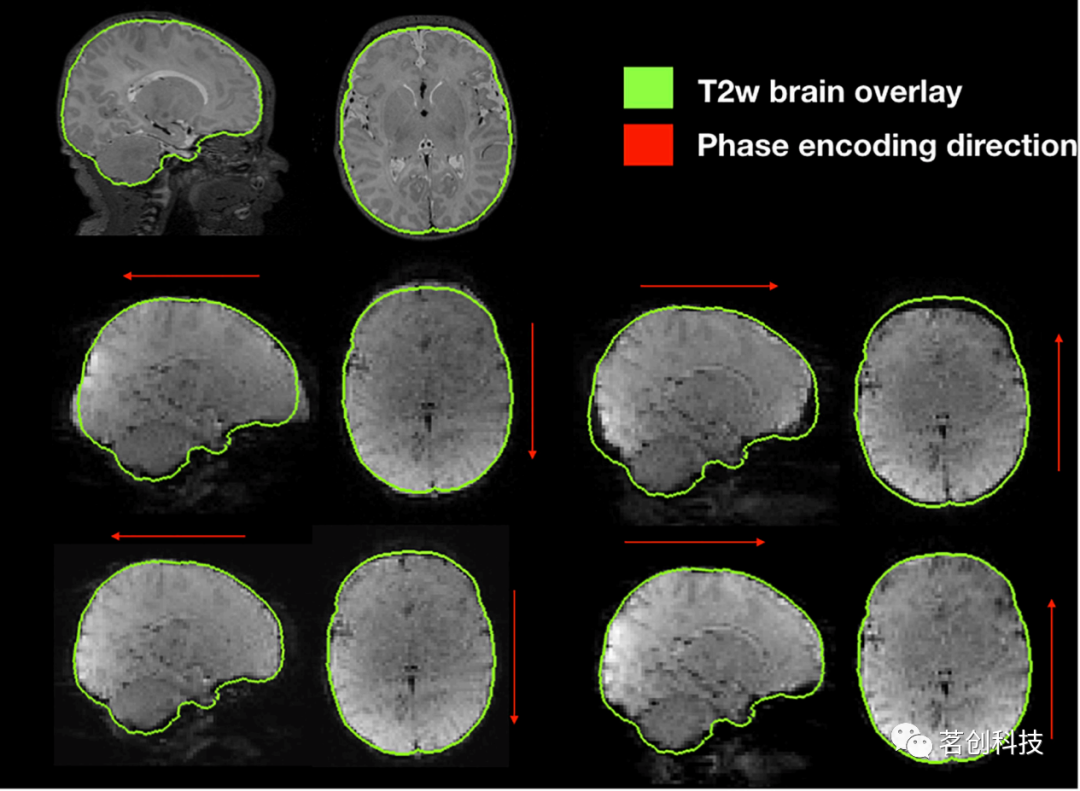

功能畸变校正

其中,一个代表性被试的功能磁化率引起的非均匀磁场校正如图8所示。与脑大小无关的GRE EPI图像,无论获取的是AP还是PA,都会在相位编码方向上发生畸变,而且在两个脑区都存在畸变。在磁化率引起的非均匀磁场畸变校正后,两次采集(AP和PA)相对于未畸变的T2加权图像呈现出相似的形态和更准确的大脑形状。

图8.磁化率引起的非均匀磁场导致沿相位编码方向的几何畸变。